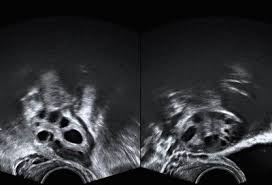

Wenn sie verdächtig aussehen Bauchwasser vorhanden ist oder Tumormarker im Blut sind muss man schnell operieren so der Gynäkologe. Da im Ultraschall eine Unterscheidung zwischen gutartiger Zyste und bösartigem Tumor schwer möglich ist werden Zysten nach dem fünfzigsten Lebensjahr meist operativ entfernt und untersucht. Ist das Gewebe bereits abgestorben muss der Eierstock entfernt werden.

Welcher Weg gewählt wird ist abhängig von der Art der Zyste den klinischen Symptomen der Länge des Bestehens der Eierstockzysten und vom Alter der Patientin Der Arzt wird dann zu einer operativen Bauchspiegelung raten wenn gutartige Geschwüre wie Gebärmutterknoten Myome oder Zysten an den Eierstöcken Beschwerden bereiten und klein genug sind um mittels Bauchspiegelung entfernt zu werden. Das Gleiche gilt wenn eine Veränderung im fortgeschrittenen Alter entdeckt wird. Lediglich im Falle von Komplikationen kommen Patientinnen nicht immer um einen Eingriff herum.

Nach 6-8 Wochen wird durch den Ultraschall. Diese bilden sich nämlich aus dem Follikelrest nach dem Eisprung.